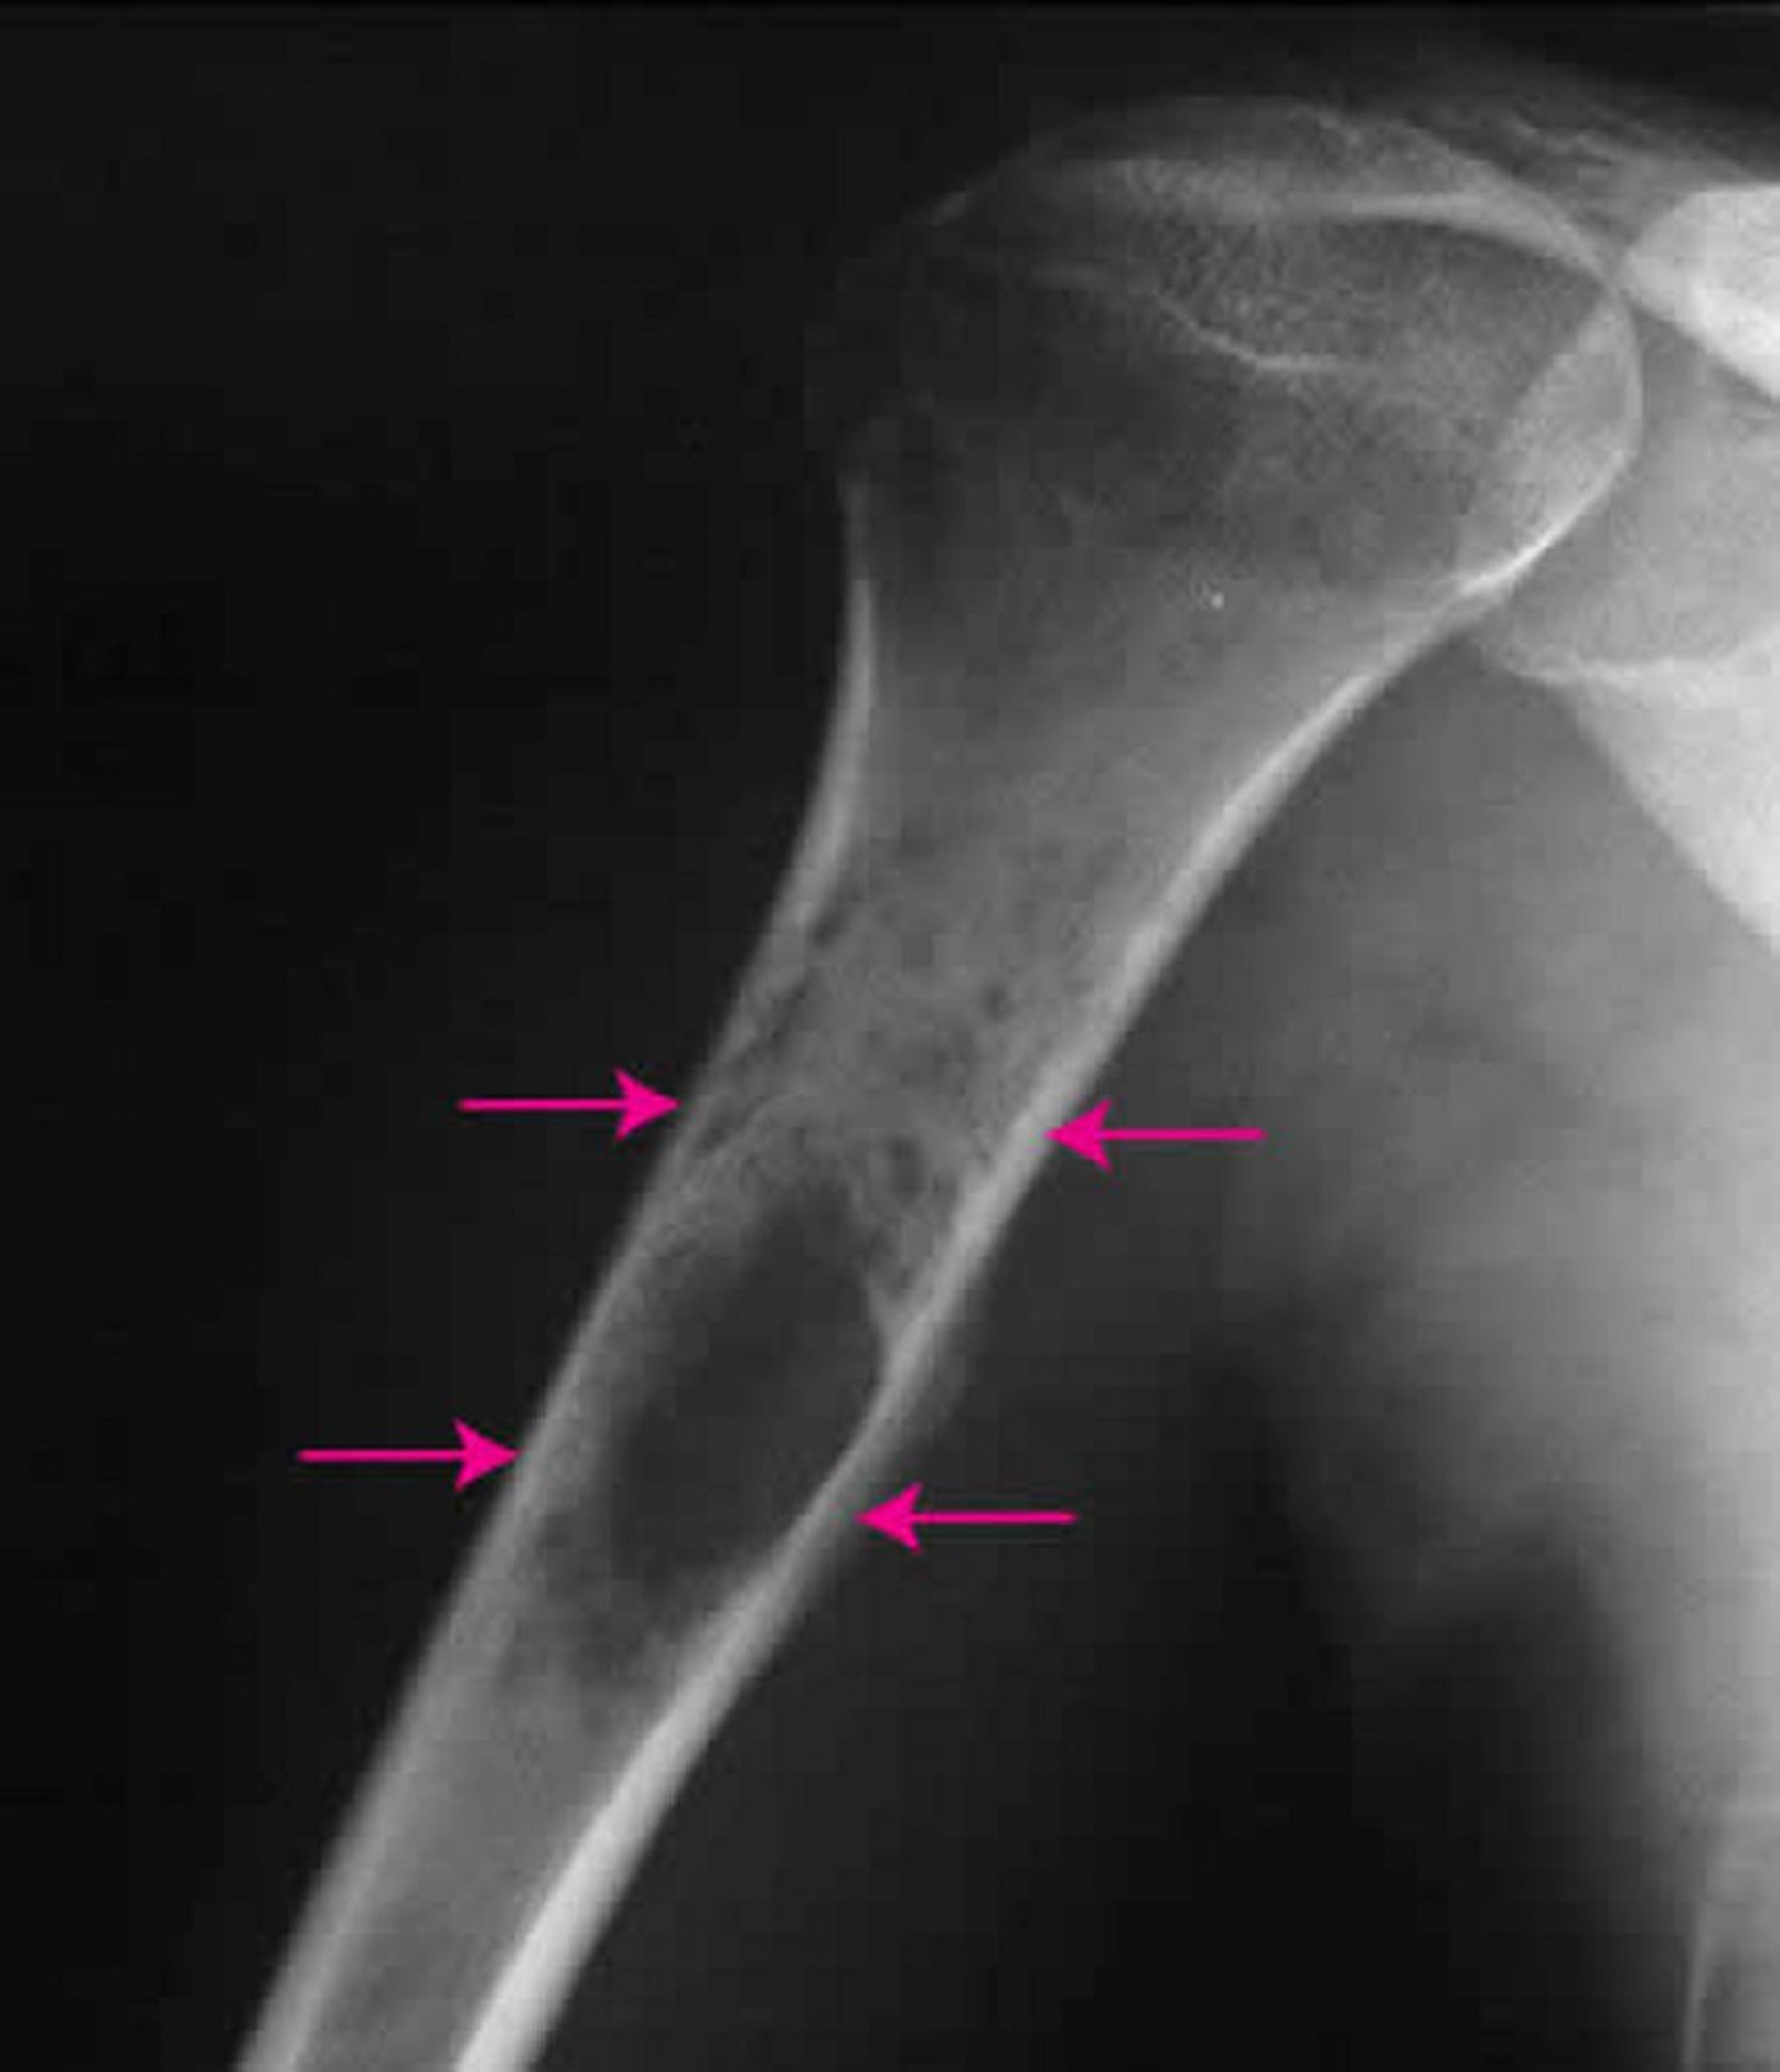

हड्डी का यूइँग सार्कोमा

कंधे का यह एक्स-रे ऊपरी बाँह की हड्डी के भीतर यूइँग सार्कोमा (तीर) को दिखाता है।

मिशेल जे. जॉयस, MD, और हैकन इलास्लैन MD के छवि सौजन्य से।